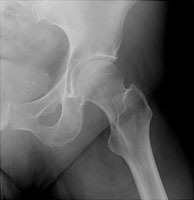

Femoral neck fractures also result from falls, especially in elderly and osteoporotic females. They are associated with radial and humeral fractures. The Garden classification is widely used to categorize these fractures. Garden I is an incomplete fracture through the femoral neck while with Garden II, the fracture is complete. With Garden III fractures, there is impaction, and with Garden IV, the femoral neck is superiorly migrated relative to the femoral head. Garden IV fractures have the highest risk of avascular necrosis.

C | AP view of a Garden IV fracture of the femoral neck. |